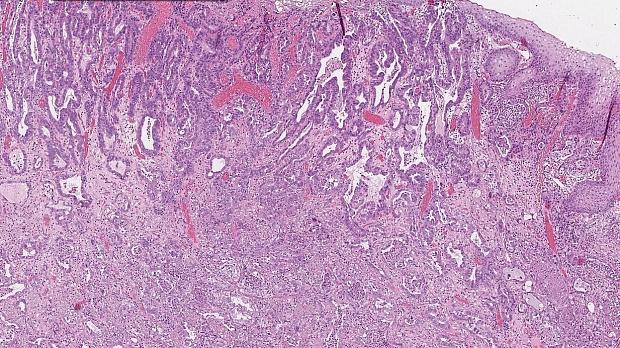

Иллюстрация №3: Рис. 3. Аденокарцинома пищевода. Окраска HE, увеличение х 100

При поступлении в нашу клинику, по результатам пересмотра предоставленного гистологического материала был подтверждён диагноз аденокарциномы (рис. 3). При повторной эзофагогастродуоденоскопии в области кардиоэзофагеального перехода было обнаружено эпителиальное образование Is типа, размерами до 15 х 20 мм, высотой до 8 мм. При осмотре в узком спектре света (NBI) с использованием функции двойного фокуса имелась отчётливая демаркационная линия между новообразованием и окружающей его слизистой оболочкой, а в его центральной части микрососудистый рисунок имел нерегулярный характер, ямочный рисунок поверхности эпителия был разрушен, что согласно VS-классификации K.Yao характерно для неопластических изменений (рис. 4 a, b). Просвет «малого» вновь сформированного желудка расправлялся не полностью, складки были утолщены, слизистая оболочка отечная, гиперемирована. Гастроэнтероанастомоз широкий, эластичный, слизистая оболочка его отечная, незначительно гиперемирована, без язв и эрозий. Слизистая оболочка анастомозированной тонкой кишки без особенностей.

Морфологическое и иммуногистохимическое заключение: тубулярная аденокарцинома пищеводно‑желудочного перехода, grade I. Опухоль прорастает в верхнюю треть подслизистого слоя (sm1), pT1b. Васкулярной инвазии не выявлено (Ly «-», V «-»), в краях препарата признаков опухолевого роста не выявлено (LM «-», VM «-»), R0 (рис. 9).